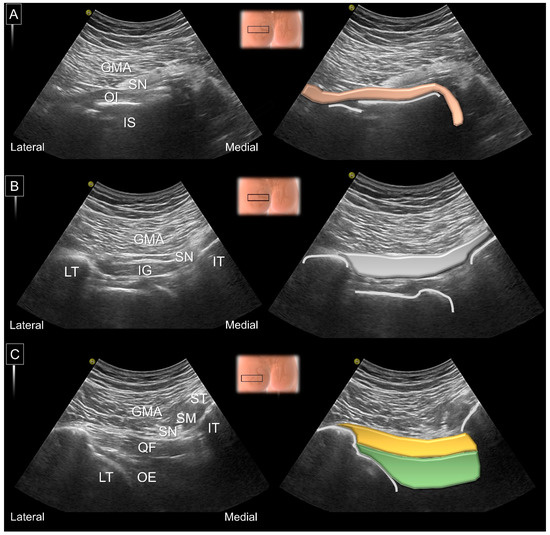

8. Dynamic Ultrasound Evaluation